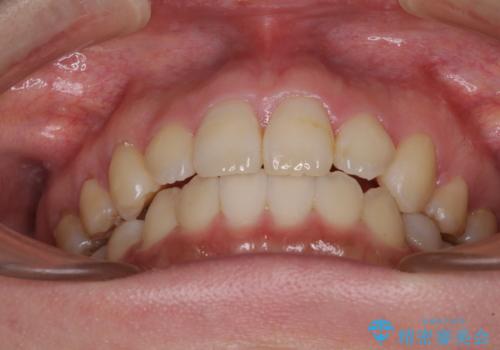

- 口元の突出感を気にして来院された患者様です。

診断の結果、上顎左右第一小臼歯4本抜歯により、叢生を解消するとともに口元を引っ込めていくことが望ましいと判断しました。

抜歯矯正による口元の改善にはワイヤー矯正が望ましいのですが、ダンサーとしての仕事を行っているため、インビザラインにて治療を行うこととしました。